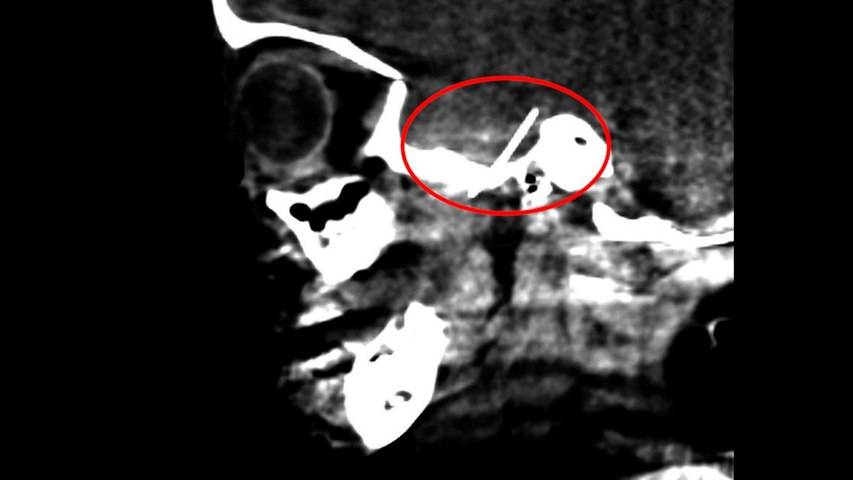

VIDEO: Salvan a una niña de 4 años que tenía una aguja...

Un curioso caso médico se produjo en el Hospital Sant Joan de Déu, de Barcelona, según informó La Vanguardia. Allí, una niña de cuatro años fue sometida a una inusual cirugía para extraerle una aguja que tenía alojada en el cerebro. La operación fue todo un éxito y la niña no tendrá más secuelas que la cicatriz que le dejó la intervención en el lado derecho de la cabeza.